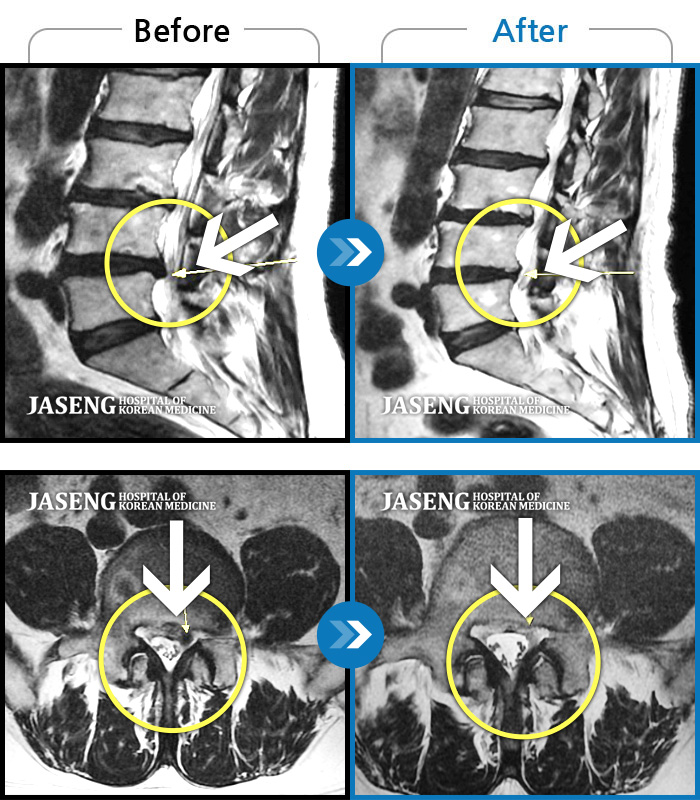

MRI 치료사례

요통과 좌측 하지부 통증